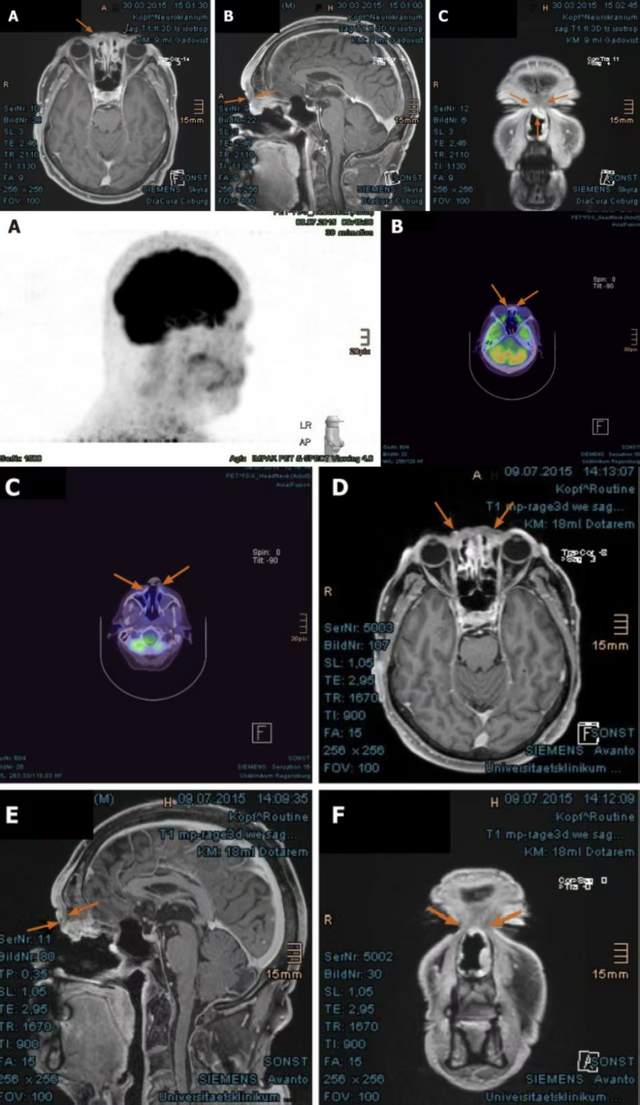

在接受质子治疗后,该患者在治疗初期鼻部肿胀,夜间有钝痛感,通过使用抗水肿药物和止痛药后症状有所缓解。质子治疗结束后3个月的首次随访显示,患者鼻梁区域的肿瘤显著缩小。8个月后肿瘤完全缓解,面部及左耳后区域的淋巴水肿通过频繁的淋巴引流按摩逐渐消退。除了持续存在的眼泪增多现象外,患者未出现感觉障碍。截至2020年。该患者一直保持无肿瘤复发,视力和听力功能也未受到影响。

该案例表明,质子治疗在肿瘤控制和生活质量方面均表现出优异的结果。虽然患者接受治疗后出现不良反应,但经过对症治疗后均缓解。